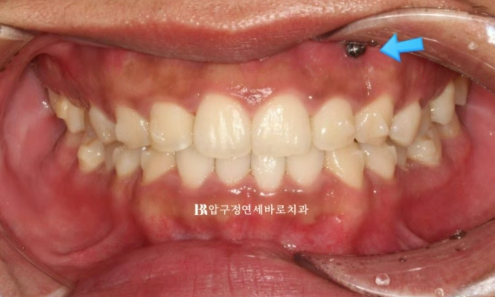

4개월 간 14개의 장치를 다 낀 후의 교합입니다.

파란 화살표 부위에 환자분이 고무줄을 열심히 걸어주었으며 4개월 간 교합평면 기울어짐, 과개교합은 잘 해결이 되었습니다

웃을 때 이제 더 이상 한쪽 치아가 내려와 보이지 않습니다.

결과도 좋고 환자분도 만족하여 재제작 없이 치료를 종료하기로 했습니다.